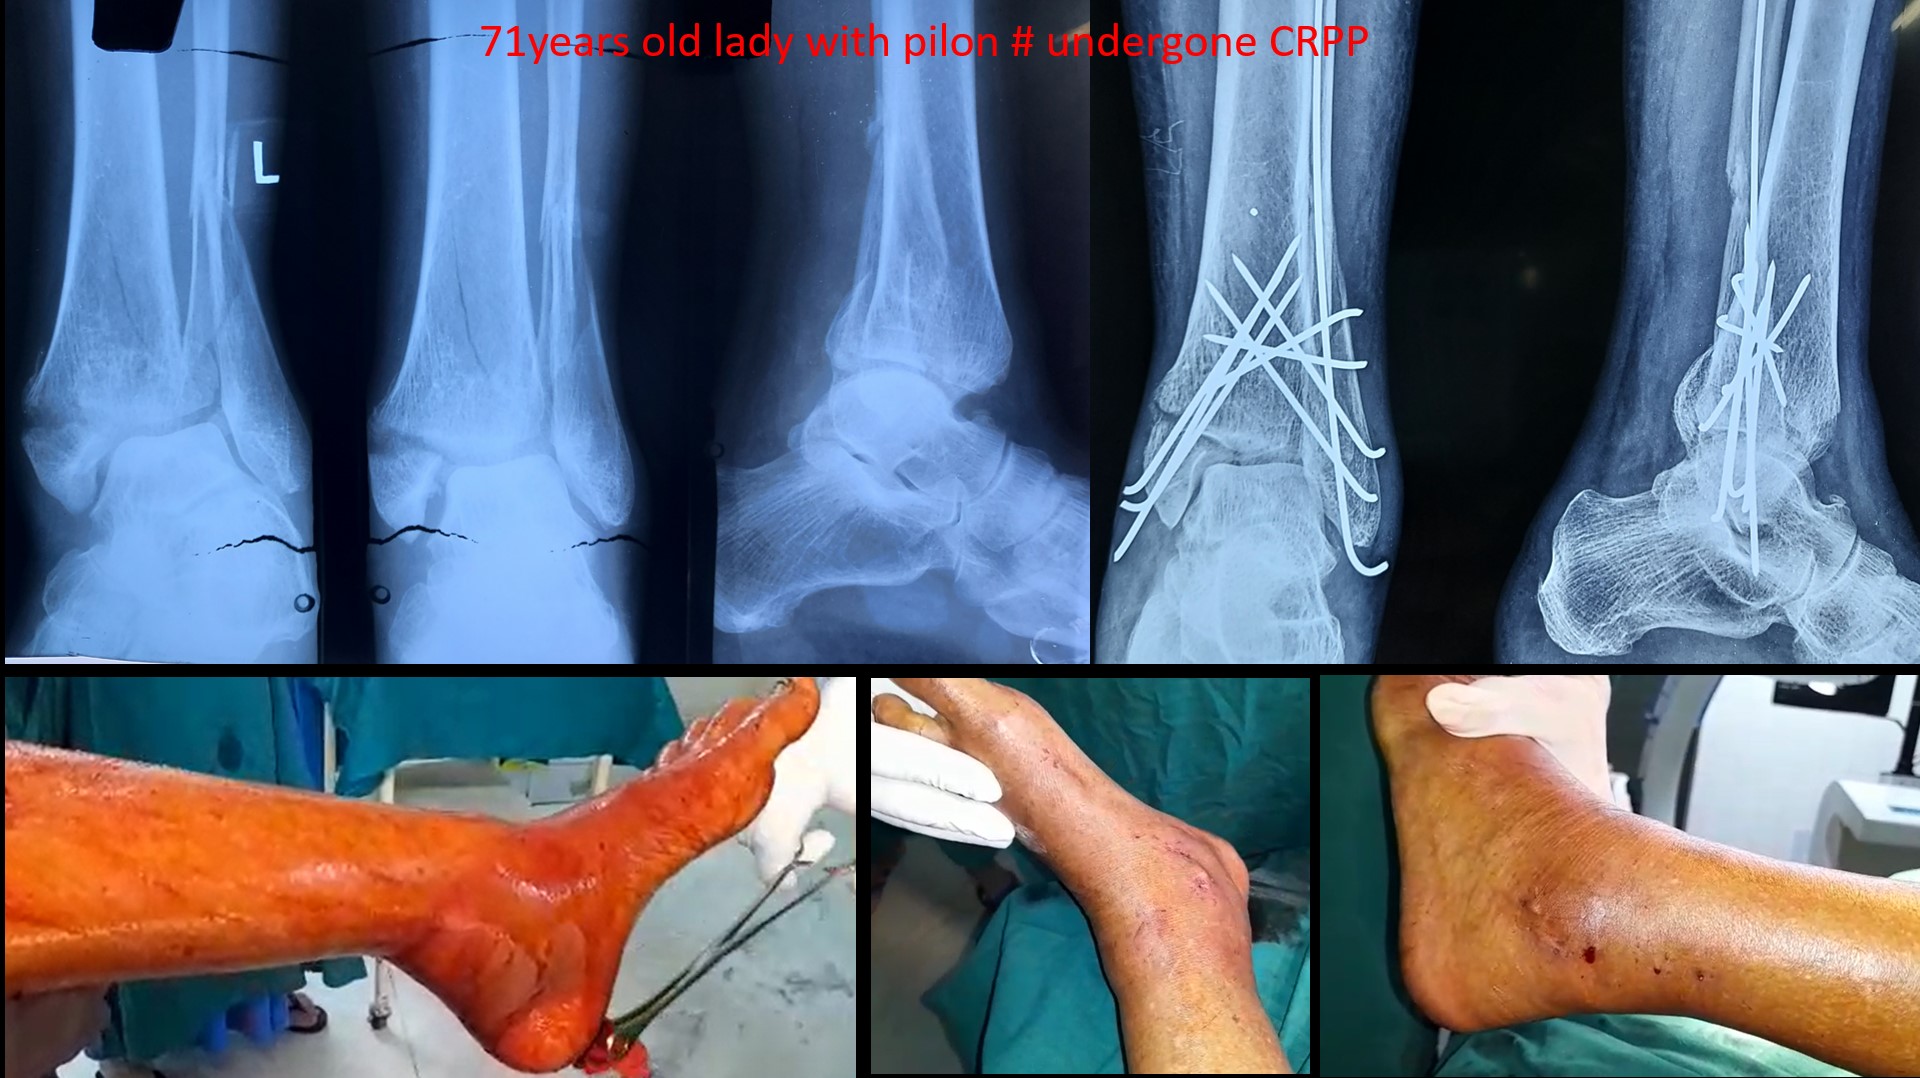

ANKLE